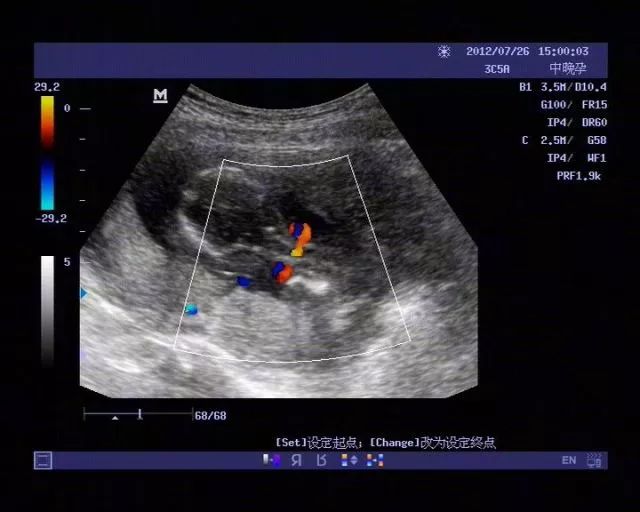

通过B超检查可清楚地看到胎儿是否有脐带绕颈情况。

用一般2D超声检查,其诊断率约为33.3%,如果应用彩色多普勒超声检查,其诊断率约为78.9%,而3D和4D超声检查的诊断率接近100%。

出现脐带绕颈时,产前可以通过B超检查胎儿身体上有无脐带压迹确诊,有经验的B超医师可以准确地测出脐带缠绕的周数。